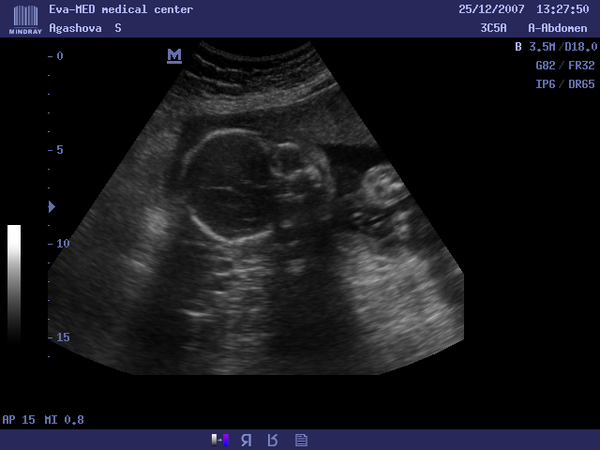

Нашла диск с фото с узи на 24 недели(25.12.2007г.),так трогательно,аж слезы текут рекой.Тогда нам сказали что у нас будет девочка,а родился мальчик)))